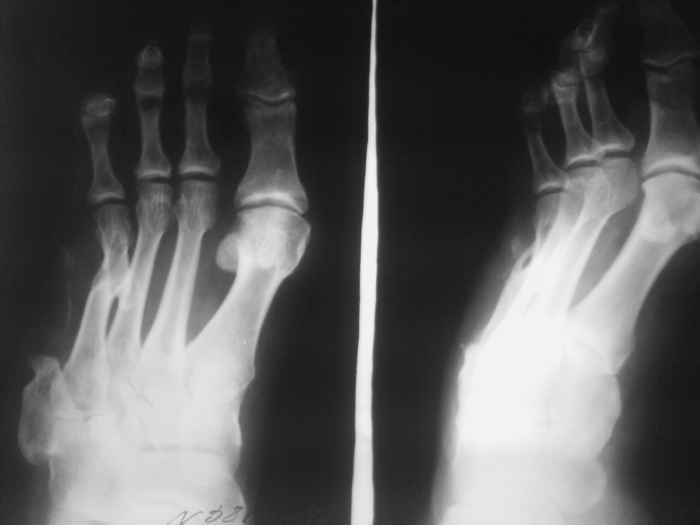

Re: Остеомиелит 4 плюсневой кости.

Спасибо за содействие )) В моем случае я не могу точно (без фистулографии, т.к. свищ закрыт) определить уровень и объем резекции кости в соответствии с будущей (надеюсь) операцией для восстановления опороспособности стопы. Или оставшихся трех лучей будет достаточно в ортопедической обуви? Предполагается резекция средней части диафиза 4 плюсневой кости с фистулонекрэктомией.

Не думаю, что потеря еще одного луча добавит опорности стопе. Как Вы планируете после резекции

восстанавливать длину плюсневой кости и добиваться сращения?

Предполагаемый общий (без деталей) план действий за 3тышшы км мне видится таким: 1.санация(нужна ли здесь резекция?),2. спейсер, 3.внешная или диафиксация. Можно добавить для стабильности и опорности на время лечения крепкую пластиковую лонгету на стопу. Кстати спейсер для костной полости не обязательно делать в виде бус.